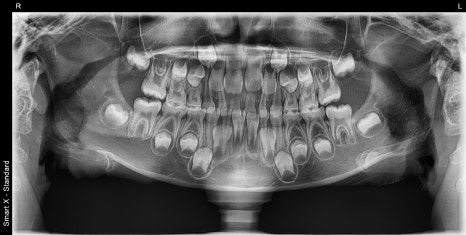

Left (panoramic X-ray): A panoramic X-ray taken at the first visit to check whether there was any damage to the teeth or jawbone due to the trauma. Fortunately, no abnormalities were found in the teeth or bones.